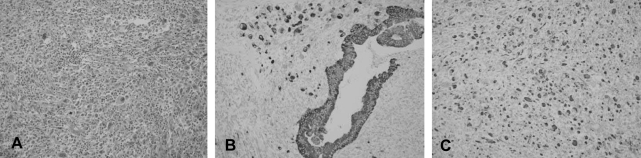

The gross pathologic findings showed a 15×8×7 cm sized, 606 gram cystic mass. It was unilocular and contained dark brown viscous material. The inner surface of the cyst was smooth except for three solid mural nodules that were 0.8, 1 and 1.5 cm in diameter, respectively. The cystic wall measured 0.7 cm at the maximum thickness. There was no evidence of capsular rupture. The mural nodules were soft and brownish pink. Microscopically, the cyst was lined by atypical columnar cells of mucinous cystadenocarcinoma (Figure 2A, 2B). The solid mural nodules showed highly pleomorphic spindle cells and anaplastic giant cells with numerous atypical mitosis, and there were intervening atypical glands of adenocarcinoma (Figure 3A). The spindle and giant cells were positive for cytokeratin, vimentin and smooth muscle actin, but negative for S-100 protein and desmin (Figure 3B, 3C). The carcinoma cells were positive for cytokeratin and they were negative for vimentin, smooth muscle actin, S-100 protein and desmin. The diagnosis of the mass was primary retroperitoneal mucinous cystadenocarcinoma with mural nodules of sarcomatoid change.

Figure 3

(A) The solid mural nodules showed highly pleomorphic spindle cells and anaplastic giant cells with numerous atypical mitosis (H&E, ×200). (B) The adenocarcinoma cells, spindle cells and giant cells were positive for cytokeratin (×200). (C) The spindle and giant cells were positive for vimentin (×200).